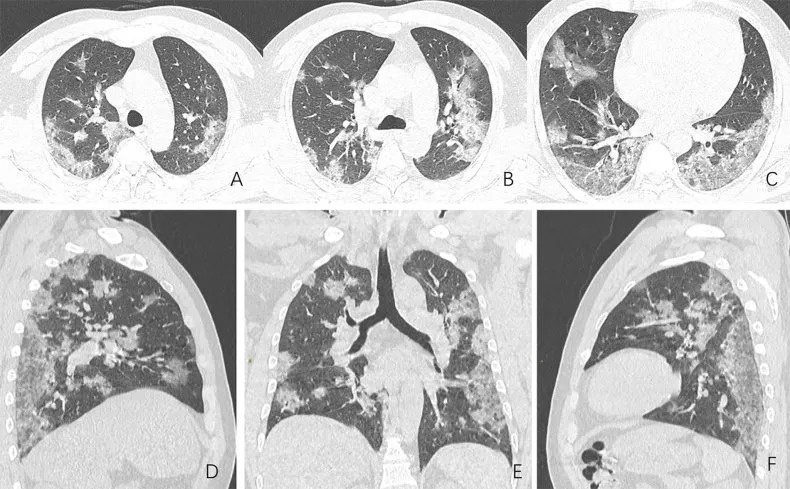

Hình ảnh chụp cắt lớp vi tính của những người nhiễm Covid-19 cho thấy virus đã tấn công và gây tổn thương nặng nề đến phổi của bệnh nhân.

Kết quả chụp CT phổi của các bệnh nhân Covid-19 thường chung đặc điểm là xuất hiện những đốm trắng.